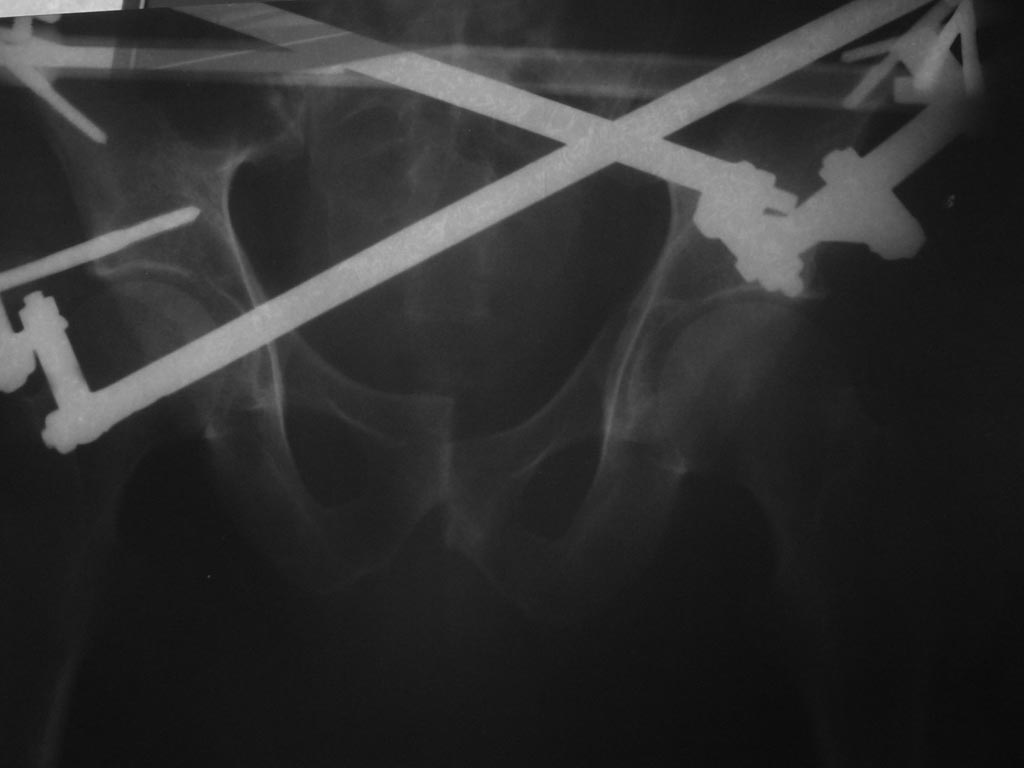

вывих половины таза. нужна репозиция. |

Я клинический ординатор по специальности травматолог-ортопед в НЦ РВХ города Иркутска. Ко мне обратился знакомый из бурятии. в начале июля этого года в результате ДТП получил травму таза (разрыв лонного сочленения и разрав кресцово подвздошного сочленения справа.Дислокация правой половины теза кверху.Вертикально нестабильное повреждение таза типа С Про месту травмы лечился на скелетном вытяжении, репозиция не достигнута. В конце июля прооперирован по месту жительства: закрытая репозиция таза, фиксация в АВФ. Репозиция не достигнута. Выисан на амбулаторное лечение. В данный момент беспокоят постоянные боли, деформация, невозможность пользоваться правой нижней конечность, и в связи со всем перечисленным проблемы с активизацией. Консультировался со старшими коллегами по поводу возможности лечения в нашей клинике. На что получил ответ что "недостаточно опыта в лечении подобных травм и их последствий". Прошу помочь в решении данного вопроса. С уважением Чингиз Бутаев.

возможно проблема не стоит выеденного яйца. представленные рентгенограммы малоинформативны, т.к. металлоконструкция закрывает КПС слева. поэтому необходимы дополнительные проекции по Judet. по представленной рентгенограмме создается впечатление, что смещение обусловлено переломом передней колонны верлужной впадины и разрывом лонного сочленения, поэтому задние отделы скомпрометированы минимально и не требуют оперативного вмешательства с уважением! Сергей.